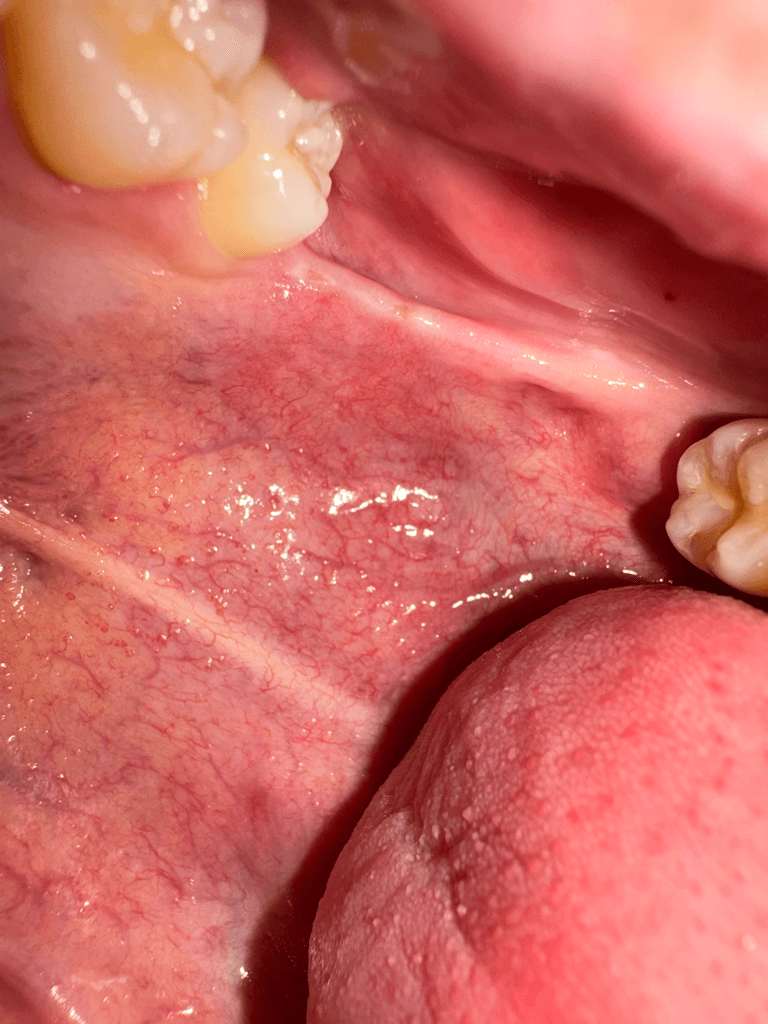

왼쪽 위아래 사랑니가 나야할 자리에 위아래로 연결된 끈 같은게 있는데 한 두달전부터 입벌릴때마다 땡기고 아픕니다. 오른쪽 아래어금니 크라운을 씌울 때 입을 계속 벌리고있었는데 그 때부터 의식하게돼서그런지 자꾸 신경쓰입니다. 사랑니가 나는 자리에도 약간 꺼끌꺼끌하게 상처같은게 나있는 것 같아요(혀로 만지면 느껴집니다.) 입을 최대한 크게 벌리면 저 끈같은게 끊어질 듯 아프고 사진도 자세히 보시면 말씀드린 끈같은것에 노란색 고른같은게 있어보입니다. 구강암같은 것일까요...? 치과에서는 별 말씀 없으셨었습니다.

1. 해당 구조는 pterygomandibular raphe라고 하며 정상 구조물입니다.

해당되는 부위는 정상적인 해부학적 구조물입니다. 해당 부위가 불편한 것처럼 느껴지는 원인은 턱관절이나 해당 조직 주변의 근육이 과 긴장되어서 일 수 있으니 턱에 가해지는 힘을 줄여보는 것을 권유드립니다. 자세한 확인을 위해서 치과에서 진료를 받아보세요

저부위에 상처가 생겨서 그러는거 같으니 당분간은 입을 크게 벌리는건 조심하시고 그쪽부위에 자극이 가지 않도록 해주시는게 좋을것같습니다.